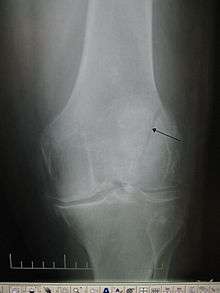

A vertical patella fracture with the fracture line marked by a black arrow